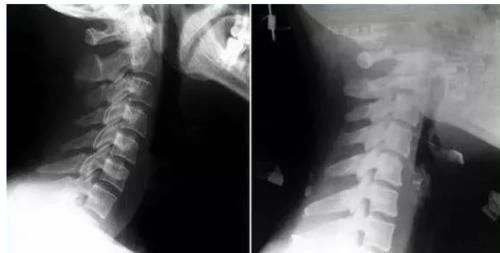

颈椎发生退行性病变时,压迫交感神经导致心脏供血不足,同时颈椎还会压迫颈椎血管,所以颈源性心脏病常常伴有脑部供血不足,眩晕等症状。颈源性心脏病与情绪无关,而是由颈椎的长期劳损导致。

而冠心病的心电图可以发现心律失常。不发作时多数无特异性。心绞痛发作时S-T段异常压低,变异型心绞痛患者出现一过性S-T段抬高。不稳定型心绞痛多有明显的S-T段压低和T波倒置。